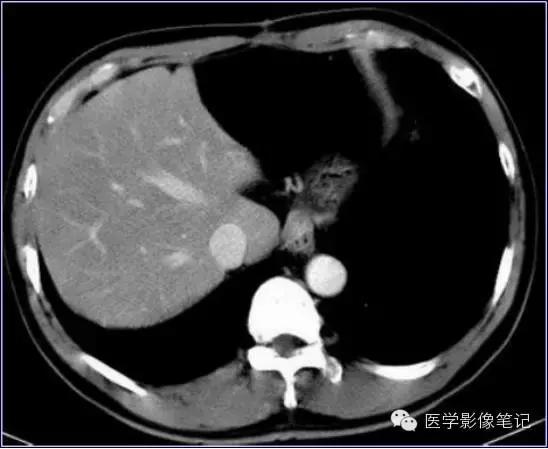

肝脏变异

獭尾肝/包围肝,见于5%的成人。

獭尾肝/包围肝

利德尔叶(Riedel’s Lobe)

肝的右下部向下如舌状突出生长的舌叶。

乳头状突

肝尾状叶结构,常误认为肿大淋巴结。

肝左叶缺如

右叶发育不全

内脏反转

咳纹肝

女性多见,由慢性咳嗽膈肌紧勒肝脏所致,也可见于过度束腰的妇女。

镰旁肝假病灶

多位于左叶内侧段或(和)左叶外侧段前缘镰状韧带旁。

机制:1、镰旁肝局部特殊血供因素;2、镰旁肝局部脂肪浸润。

来源:医学影像笔记